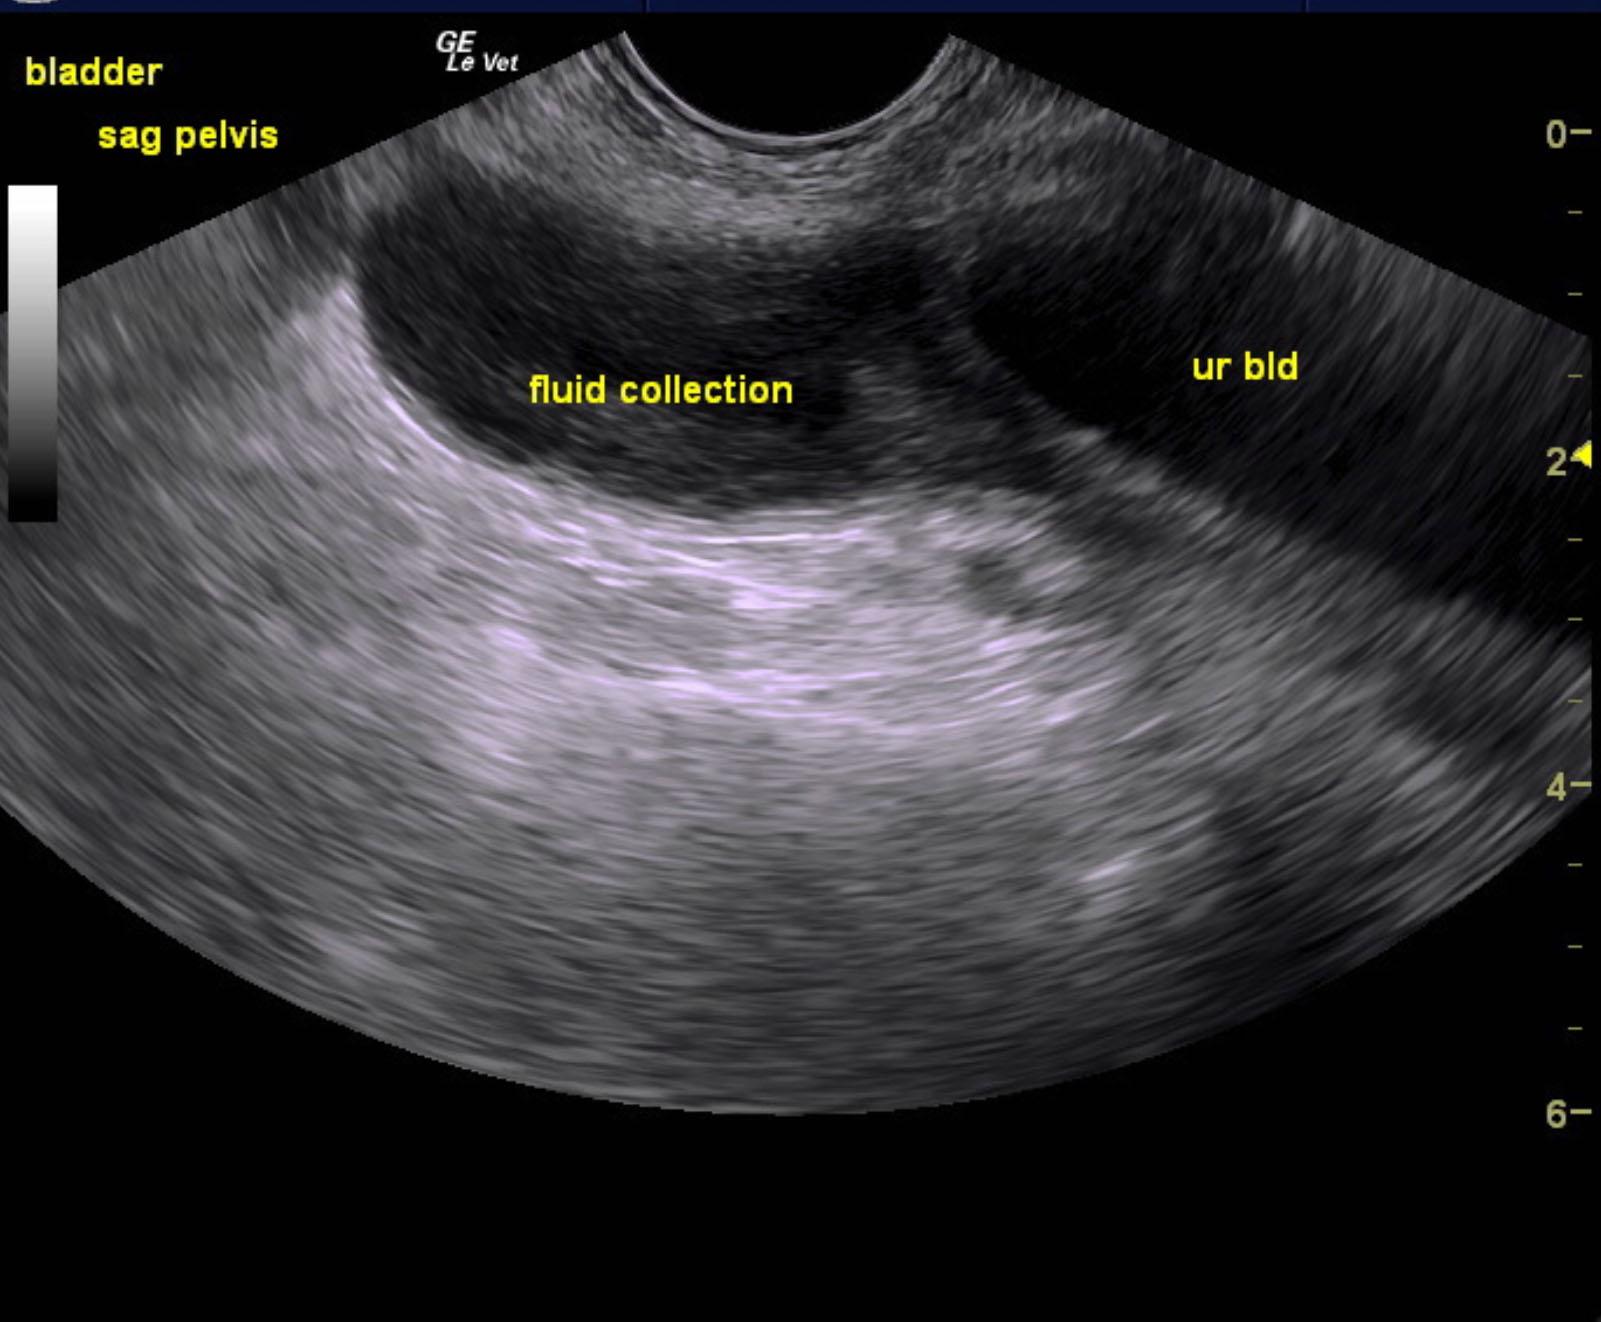

The urinary bladder itself presented minor thickening and minor debris. A tubular structure was noted in a position between the colon and the urinary bladder with dilation.

Purulent material was obtained on ultrasound-guided centesis without complications. However, reactive mesentery was noted throughout the pelvis. The position of this tube would fit with a uterus. This patient may be a hermaphrodite with secondary pyometra. I cannot make a direct connection from the tubular structure to the prostate itself as they appear to be separate. I recommend exploratory surgery with removal of this structure. The ureters do not appear to be involved. The position and structure would be that of a uterus. Therefore, treatment for pancreatitis and localized infection in the region of the pelvis would be recommended with IV fluid support, broad spectrum antibiotics such as Enrofloxacin and Clindamycin combination as well as exploratory surgery. If the tubular structure is confirmed to be a uterus and hermaphroditism then examination for possible ovaries would also be warranted even though none were visible in the image set. Regardless, this tubular structure necessitates surgical resection.

Purulent material was obtained on ultrasound-guided centesis without complications.